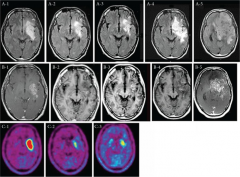

总结了日本BNCT治疗恶性神经胶质瘤的临床研究。尽管临床研究中的入选患者人数很少,并且包括了各种方案,但中位生存时间为10.8至27.1个月。该结果令人鼓舞,并且鼓舞了医学机构使用基于加速器的BNCT进行的随机II期研究。